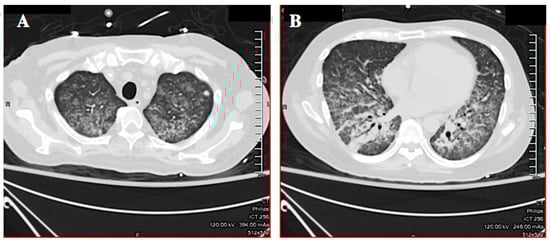

Initial laboratory results were: White cell count 19.5 K/µL (reference range (RR) 3.4–10.4 K/µL) with 51% bands, 38% neutrophils, 3% lymphocytes, 1% eosinophils; hemoglobin 11.8 g/dL (RR 12.8-17.1); platelets 214 K/µL (RR 140-377 K/µL); creatinine 1.2 mg/dL (RR 0.6–1.3 mg/dL), bilirubin 1.2 mg/dL (RR 0.2–1.2 mg/dL); alanine aminotransferase 71 IU/L (RR <46 IU/L); aspartate aminotransferase 47 IU/L (RR <36 IU/L) and alkaline phosphatase 124 IU/L (RR 45–117 IU/L). A CT scan of the chest showed interval development of diffuse ground glass opacities (likely alveolar hemorrhage), interlobular septal thickening, and a single 9 mm right middle lobe cavitary lesion (Figure 2A,B). The patient was admitted to the medical intensive care unit with septic shock. He was started on cefepime, vancomycin, and metronidazole. The next day he required intubation for hypoxemic respiratory failure. Bronchoscopy showed a normal airway with fresh and old blood present, but without an obvious source of bleeding. The differential diagnosis for the hemoptysis considered at the time was tuberculosis, atypical mycobacterial infection, bacterial pneumonia, vasculitis, and Pneumocystis jiroveci pneumonia. A punch biopsy of the abdominal rash was performed.

Figure 2. Case 1: CT scan of the chest showing diffuse ground glass airspace opacities, interlobular septal thickening (A), and a right middle lobe cavitary lesion (B). The airspace opacities suggested diffuse alveolar hemorrhage.